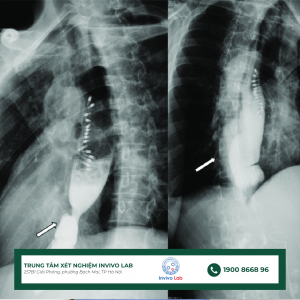

Chụp x quang thực quản giúp chẩn đoán các bệnh lý gây ra các triệu chứng như khó nuốt

Trào ngược dạ dày thực quản không chỉ gây khó chịu mà còn tiềm ẩn nguy cơ biến chứng nghiêm trọng nếu không được phát hiện kịp thời. Nhận biết sớm các dấu hiệu như ợ nóng, ợ chua, đau thượng vị, buồn nôn hay khàn giọng, đồng thời áp dụng các phương pháp chẩn đoán hiện đại như nội soi, đo pH, chụp X-quang sẽ giúp kiểm soát bệnh hiệu quả. Việc tầm soát định kỳ và điều chỉnh lối sống, chế độ ăn uống là chìa khóa bảo vệ sức khỏe tiêu hóa và nâng cao chất lượng cuộc sống.